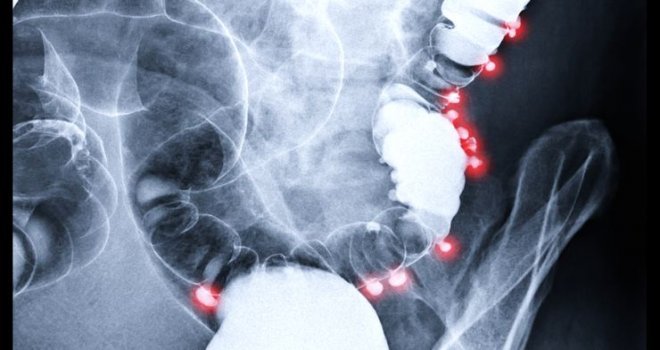

Son 15 yıldır ölümler anal kanser yüzünden gerçekleşiyor

Anal kanseri, tüm kanser teşhislerinin sadece yüzde ikisini oluşturan, nispeten nadir görülen bir hastalık şeklidir. Neredeyse tüm anal kanseri vakalarına cinsel açıdan aktif kişilerin yüzde 80’ini etkileyen papilloma virüsü (HPV) neden olur ve kendi içinde 100 farklı tipi vardır.

Ulusal Kanser Enstitüsü Dergisi'nde yayınlanan yeni araştırmanın bulguları da özellikle anal kanser oranlarında dik bir artış izlendiği yönünde.2001 ve 2016 yılları arasında toplam 68.809 kişiye anal kanser teşhisi kondu ve bunlardan 12.111’i bu hastalıktan öldü.Teşhisler ve ölümler her yıl yaklaşık yüzde üç arttı; elimizdeki bu yeni araştırmalara göre anal kanseri, günümüzde en hızlı yayılan kanser türlerinden biri. Anal kanserine erken teşhis konulduğunda sonuçlar çok daha iyi olur ve hastanın hayatta kalma oranı yaklaşık yüzde 80'e kadar artar.

Hastalık lenf bezlerine yayıldığında ise bu oran yüzde 60'a düşer.

Anal kanserinin belirtileri aslında oldukça belirgindir; anal bölgede ağrı, basınç veya topaklar, sıra dışı akıntı, kanama veya bağırsak hareketlerinde değişiklikler gibi diğer daha genel koşullarla kolayca karıştırılabilirler.

Anal seks, anal kanseri gelişimi için önemli bir risk faktörüdür ve hastalar risk faktörlerini doktorlarına açıklamakta tereddüt edebilirler. Bu da tedavi için gerekli zamanın daralmasına yol açar. Icahn Tıp Fakültesi’nde doçent olan kıdemli çalışma yazarı Dr. Keith Sigel, “Bazı yüksek riskli gruplar dışında, şu anda anal kanseri için hastalar arasında tarama yapılmıyor ancak bu çalışmanın sonuçları daha geniş taramaların değerlendirilmesi gerektiğini gösteriyor” dedi.